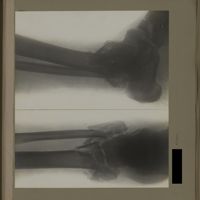

0134 - Page 22 - [Radiographies du coude et du tiers supérieur de l'avant-bras]0134 - Page 22 - [Radiographies du coude et du tiers supérieur de l'avant-bras]

0139 - Page 27 - [Radiographies du coude]0139 - Page 27 - [Radiographies du coude]

0144 - Page 32 - [Radiographies du coude]0144 - Page 32 - [Radiographies du coude]

0153 - Page 41 - [Radiographies du coude]0153 - Page 41 - [Radiographies du coude]

0175 - Page 63 - [Radiographies du coude]0175 - Page 63 - [Radiographies du coude]

0187 - Page 75 - [Radiographie du coude]0187 - Page 75 - [Radiographie du coude]

0198 - Page 86 - [Radiographies du coude et de l'avant-bras]0198 - Page 86 - [Radiographies du coude et de l'avant-bras]

0201 - Page 89 - [Radiographies du coude]0201 - Page 89 - [Radiographies du coude]